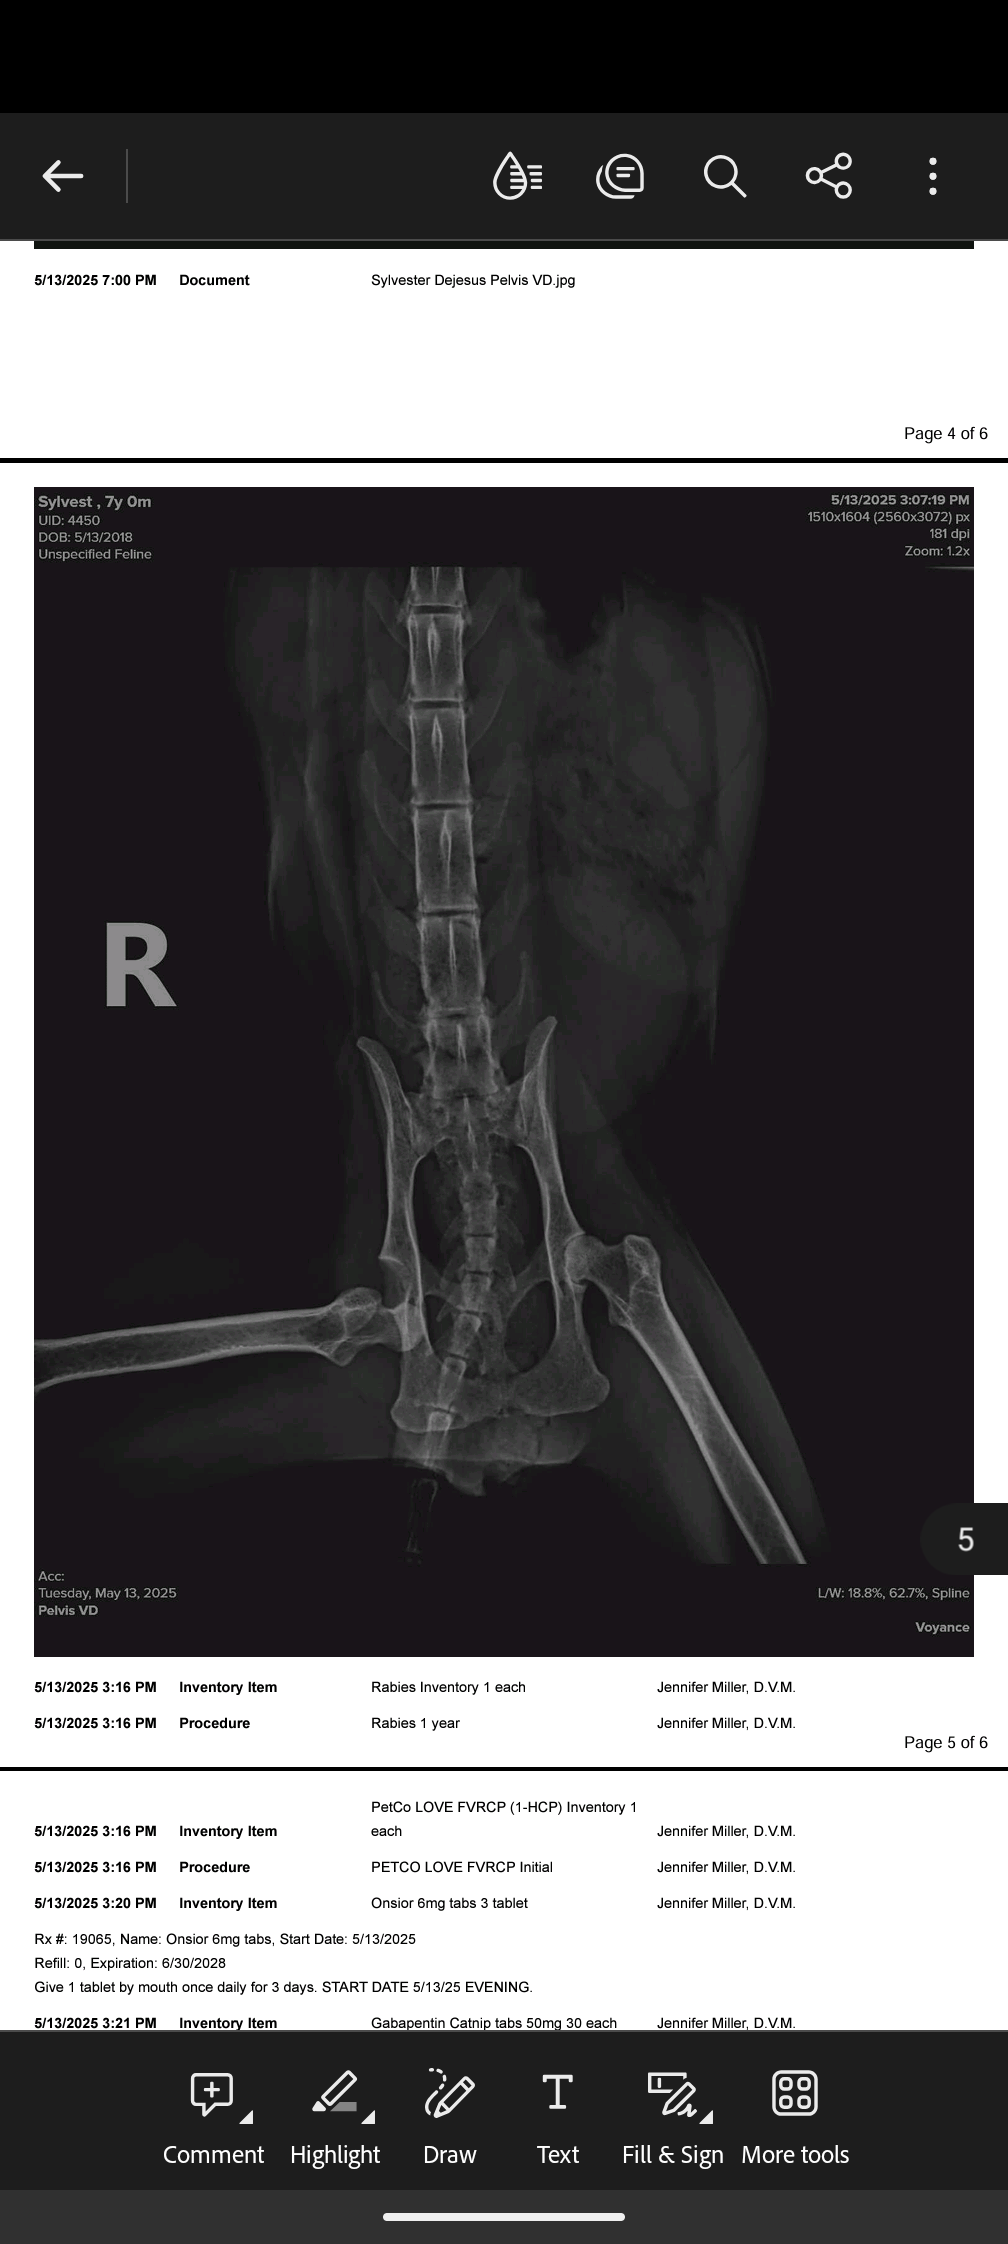

Hi, my name is Michael DeJesus, and I’m raising funds to help my cat Sylvester get life-saving surgery. Sylvester recently injured his leg after jumping off the kitchen counter, and unfortunately, the damage is too severe to heal. The vet has told us that the only option is to amputate his leg to stop the pain and give him a chance to live a healthy life.